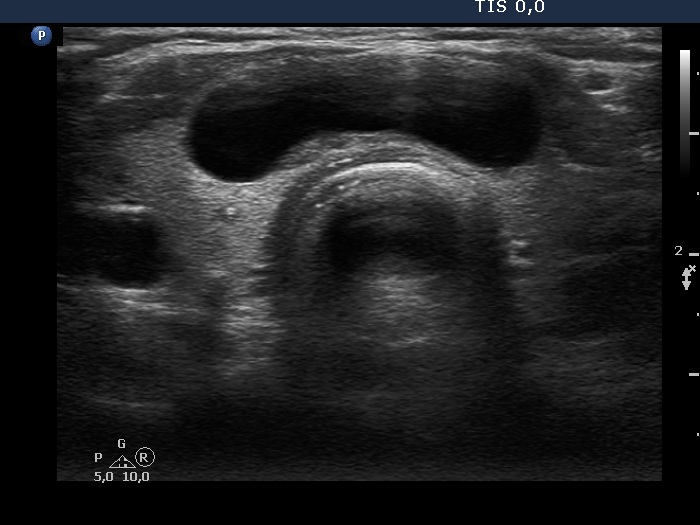

Intranodular hyperechogenic figures - case 1158 (ultrasonographic picture 3)

Isthmus, transverse view. There is a dominantly cystic nodule.